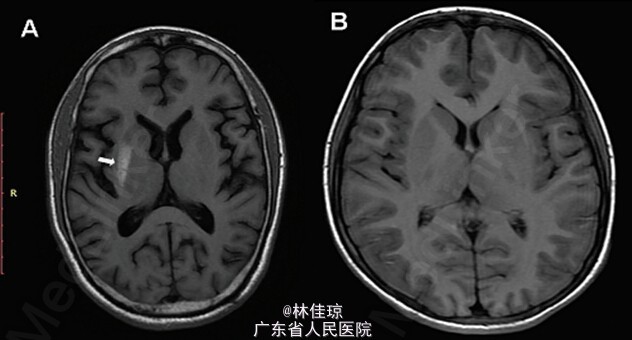

神清,颅神经检查正常,左侧肢体的舞蹈样动作及不自主运动无法自行控制,但在睡眠中停止。 随机血糖:527mg/l,酮体(-)(0.5mmol/l/),HbA1c 10.3%,静脉pH值7.37。 头颅 MRI:T1 加权成像提示右侧壳核高信号(图 A),T2加权加权成像显示未见显著信号异常。

诊断:糖尿病非酮症性高渗状态所致偏侧舞蹈症。 给予每日2次预混胰岛素制剂,1周后,血糖控制正常。患者的不自主运动减少,在10天后第一次复诊患者症状完全消失。接下来的随访中,2个月后, MRI 仍然显示异常,6个月后,MRI 显示高信号病灶消失(图 B), 未显示异常。